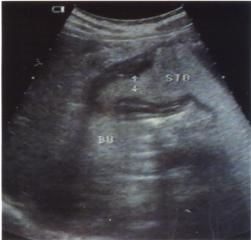

三、纖維胃鏡檢查 爭取於12-24小時內進行,對本病診斷有重要參考價值,鏡下可見胃黏膜充血水腫,點片狀糜爛,大小不等的多發性潰瘍,潰瘍面可有新鮮出血塊。